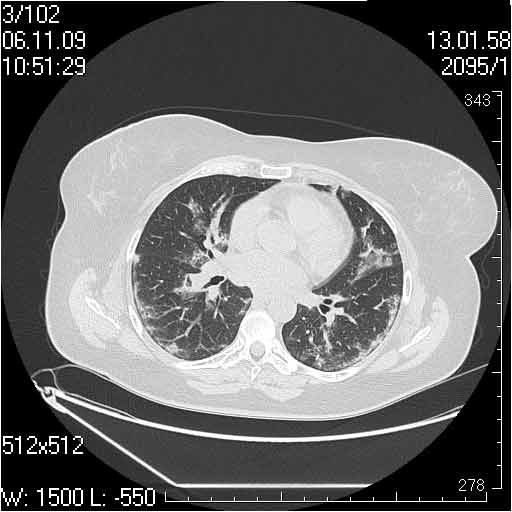

Случай №3

Женщина 51 год

Случай 3:смешанные изменения; подходят для интерстициальной пневмонии, тактика аналогична случаю 1.